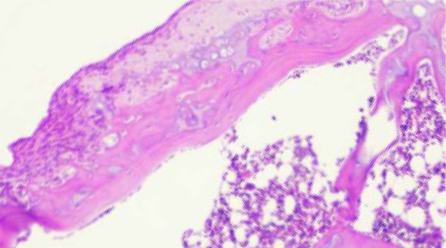

Eine Laborstudie hat gezeigt, dass Algyl GGP bei der Behandlung von Kniearthrose signifikant wirksamer ist als monokomponentale Hyaluronsäure oder Kochsalzlösung und zu einer Rückbildung degenerativer Knorpelveränderungen führt⁶. In der orthopädischen Praxis wurde Algyl GGP bei über 200.000 Patienten mit Gonarthrose eingesetzt und erwies sich als wirksam und sicher – der Effekt war langanhaltend. Ein Sicherheitszertifikat (Safety Report) bestätigt, dass bei der Anwendung keine unerwünschten Wirkungen wie Gelenkschmerzen, Schwellungen, Reaktionen an der Injektionsstelle oder andere Komplikationen auftraten.

Abb. 1: Nach der Anwendung der physiologischen Lösung wurde die Knorpelerosion bei OA nicht verbessert. Abb. 1: Nach der Anwendung der physiologischen Lösung wurde die Knorpelerosion bei OA nicht verbessert.

Abb. 2: Nach der Anwendung von HA Verbesserung, aber die Erosionen bleiben bestehen. Abb. 2: Nach der Anwendung von HA Verbesserung, aber die Erosionen bleiben bestehen.

Abb. 3: Nach der Anwendung von Algyl GGP glatte Oberfläche = laufende Regeneration. Abb. 3: Nach der Anwendung von Algyl GGP glatte Oberfläche = laufende Regeneration.